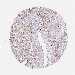

PROSTATE CANCER - Protein expressioni

A mouse-over function shows sample information and annotation data. Click on an image to view it in a full screen mode. Samples can be filtered based on level of antibody staining by selecting one or several of the following categories: high, medium, low and not detected. The assay and annotation is described here.

Note that samples used for immunohistochemistry by the Human Protein Atlas do not correspond to samples in the TCGA dataset.

Antibody stainingi

Antibody staining in the annotated cell types in the current human tissue is reported as not detected, low, medium, or high, based on conventional immunohistochemistry profiling in selected tissues. This score is based on the combination of the staining intensity and fraction of stained cells.

Each image is clickable and will lead to virtual microscopy that enables deeper exploration of all samples and also displays staining intensity scores, fraction scores and subcellular localization as well as patient and tissue information for each sample.

Antibody HPA041328

Antibody HPA044225

Staining

High

Medium

Low

Not detected

Intensity

Strong

Moderate

Weak

Negative

Quantity

>75%

75%-25%

<25%

None

Location

Nuclear

Cytoplasmic/membranous

Cytoplasmic/membranous,nuclear

Adenocarcinoma, NOS

Adenocarcinoma, High grade

Adenocarcinoma, Low grade